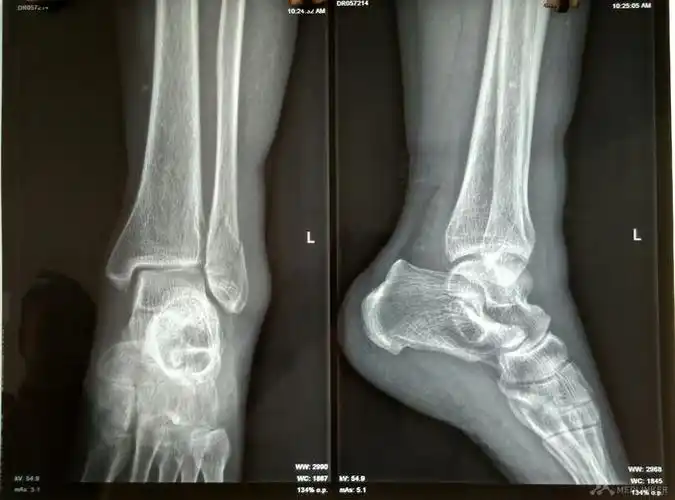

左踝关节骨折脱位